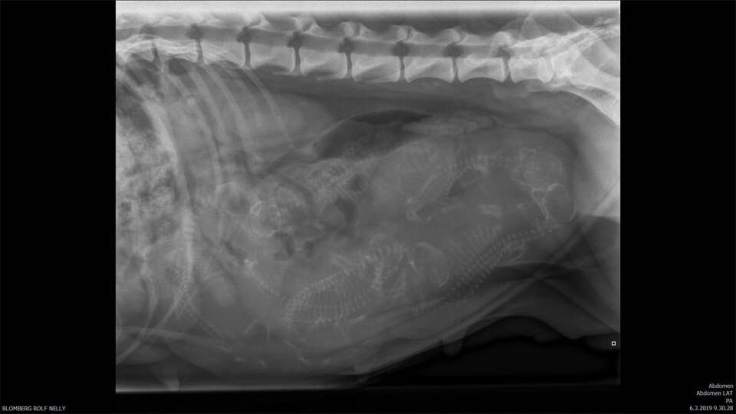

Nelly odottaa 6 pentuaan syntyväksi ensi viikon lopulla, ja voi oikein hyvin. Odotus on sujunut hienosti ja Nelly on ollut pirteän ja onnellisen oloinen koko ajan. Noomikin on oppinut kunnioittamaan mammaansa, vaikka vauhtia sillä on edelleen erittäin paljon ja itsehillintää ei ollenkaan… Siksipä niitä on pidetty ulkona erikseen, että vauhti pysyy ainakin Nellyllä hillittynä. Noomilla alkoi viikonloppuna juoksut hieman etuajassa, ja jouduimme siirtämään suunniteltua sterkkausta muutamalla viikolla eteenpäin. Eli Noomia emme aio pennuttaa (nyyh…), mutta sen siskolle Ainolle (Flower Rock’s Never Say Never) suunnitellaan pentuja vuoden päähän Moisionmäellä.